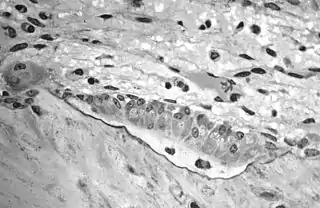

استئوبلاستها سلولهایی هستند که بخش ماتریکس پروتئینی استخوان مانند کلاژن و ماتریکس های بین سلولی را میسازند. این سلولها به صورت معمول همواره در حال ساخت استخوان هستند و چون از سوی دیگر استئوکلاستها نیز همیشه فعالند برآیند فعالیت این دو نوع سلول بازسازی مداوم استخوان است.

سلولهایی چندضلعی با آنزیم فسفاتاز قلیایی فراوان و هستهای که در خارج از مرکز سلول قرار دارد. این سلولها در محلی که فعالیت استخوانسازی زیاد است فراواناند و دارای شبکه آندوپلاسمی ناصاف و دستگاه گلژی هستند. این دو ارگان نشان دهنده فعالیتهای ترشحیاند، به همین دلیل حبابهای ترشحی بسیاری در این سلولها دیده میشود.